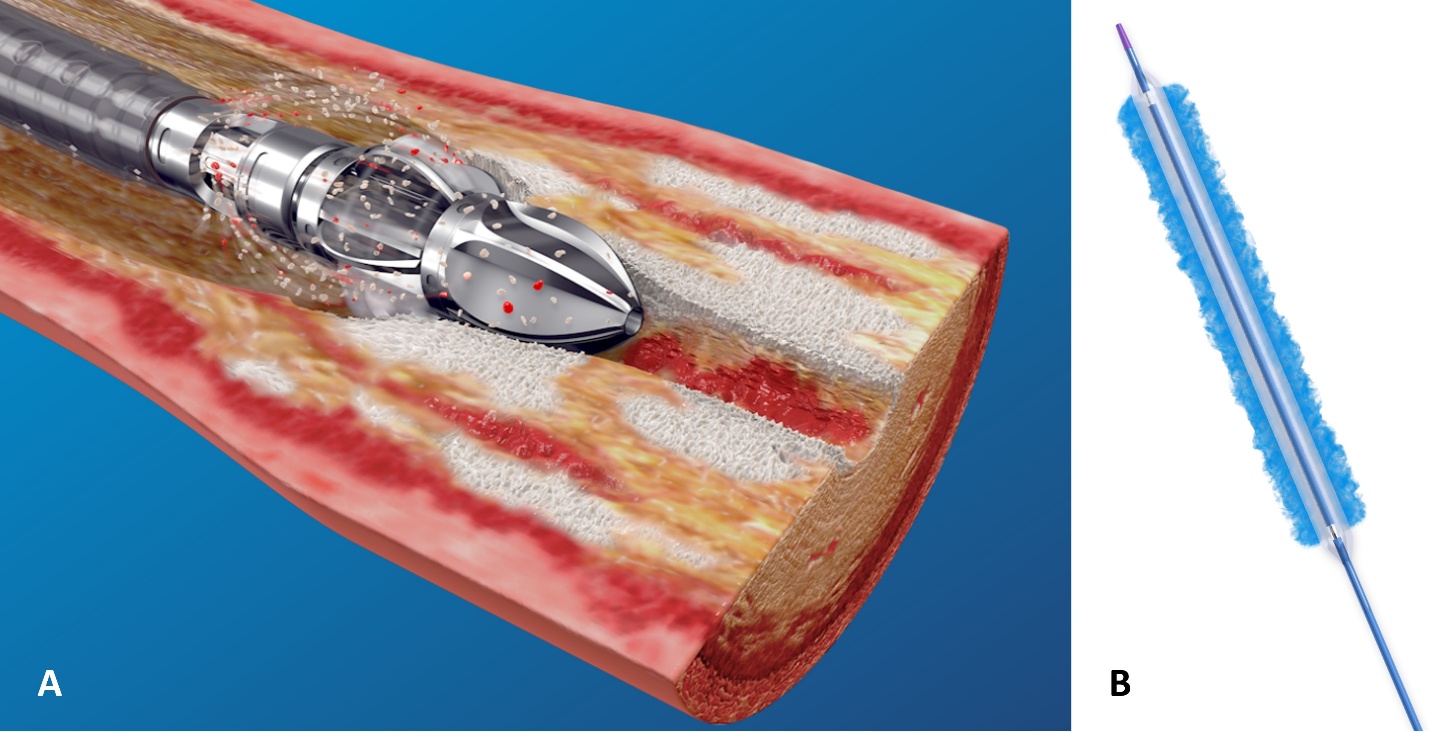

Phẫu thuật cắt bỏ hoàn toàn khối u vẫn là phương pháp điều trị được ưu tiên bên cạnh các lựa chọn xạ trị, với tiên lượng nhìn chung thuận lợi. Tuy nhiên, để đạt được mục tiêu lấy bỏ triệt để khối u đồng thời đảm bảo yếu tố thẩm mỹ cho người bệnh, các đường mổ nội soi có hỗ trợ khoan được ưu tiên thay cho đường mổ hở, giúp tiếp cận tổn thương hiệu quả và ít xâm lấn hơn.

Với kỹ thuật phẫu thuật mới kết hợp sử dụng mũi khoan kim cương, phẫu thuật viên có thể đưa dụng cụ vào trong xoang một cách thuận lợi, đồng thời tăng khả năng quan sát và tiếp cận để xử trí các khối u nằm ở thành trước dưới hoặc thành trong dưới của xoang hàm. Việc khoan mở thành trong dưới xoang hàm giúp các thao tác phẫu thuật được thực hiện dễ dàng hơn nhờ phẫu trường rộng và cho phép sử dụng dụng cụ linh hoạt. Ngoài ra, kỹ thuật này còn giúp mở rộng lỗ thông xoang hàm, tạo điều kiện thuận lợi cho việc súc rửa và vệ sinh lòng xoang sau mổ, từ đó góp phần thúc đẩy quá trình lành thương.

Phẫu thuật nội soi Denker cải tiến, có hỗ trợ khoan kim cương, không chỉ khắc phục những hạn chế của đường mổ hở và nội soi mũi xoang kinh điển mà còn mở rộng chỉ định trong xử trí các khối u lành tính và ác tính tại xoang hàm, hố chân bướm-khẩu cái và hố dưới thái dương. Việc triển khai thường quy kỹ thuật này khẳng định năng lực chuyên môn và định hướng phát triển các phương pháp phẫu thuật hiện đại, ít xâm lấn của Bệnh viện Trường Đại học Y Dược Huế, góp phần tối ưu hóa kết quả điều trị, rút ngắn thời gian nằm viện và nâng cao chất lượng sống cho người bệnh